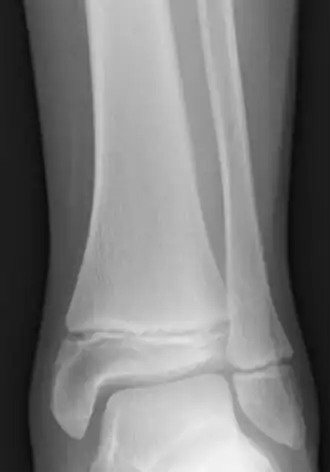

Les fractures de Salter-Harris sont des fractures impliquant les plaques épiphysaires et qui interférent avec la croissance, la taille ou les fonctions physiologiques[13].

- ↑ Crowder et Austin, « Age ranges of epiphyseal fusion in the distal tibia and fibula of contemporary males and females », Journal of Forensic Sciences, vol. 50, no 5, , p. 1001–7 (PMID 16225203, DOI 10.1520/JFS2004542) :

« complete fusion in females occurs as early as 12 years in the distal tibia and fibula. All females demonstrated complete fusion by 18 years with no significant differences between ancestral groups. Complete fusion in males occurs as early as 14 years in both epiphyses. All males demonstrated complete fusion by 19 years »